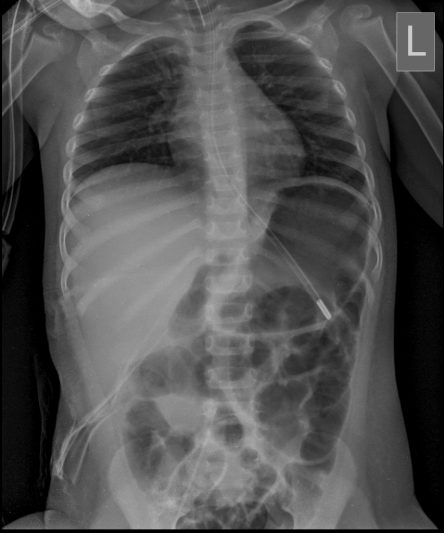

Microskan with Ultra high frequency can take the Lateral Lumbar Spine image of a 90 kg Patient with the correct image receptor